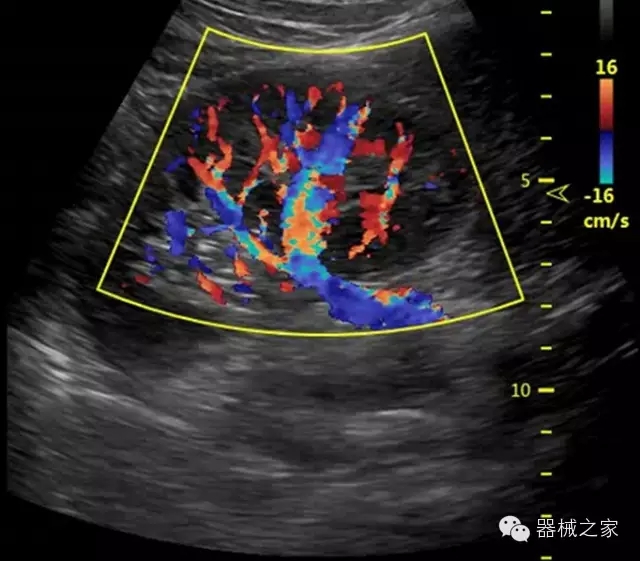

臨床圖片賞析

·獨(dú)有的RF平臺(tái)提高微小細(xì)節(jié)顯示、圖像對(duì)比度和邊界清晰度;

·特有的XCEN探頭,超寬的帶寬,表現(xiàn)更高分辨率和對(duì)比度;

·單晶純凈波探頭提供更佳的穿透力和彩色敏感度;

·獨(dú)有RF敏感血流使得心臟血流完美呈現(xiàn);